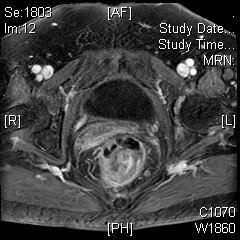

直腸系膜內的淋巴結直迫系膜筋膜 – 需考慮術前新輔助治療